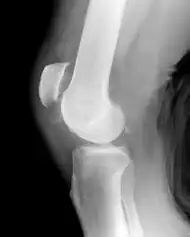

| Patellar tendon rupture showing a marked distance between the tibial tuberosity and the bottom of the knee cap. | |

Patellar tendon rupture can usually be diagnosed by physical examination. The most common signs are: tenderness, the tendon's loss of tone, loss of ability to raise the straight leg and observation of the high-riding patella. Radiographically, patella alta can be detected using the Insall and Salvati method when the patella is shorter than its tendon. Partial tears may be visualized using MRI scans.[4]